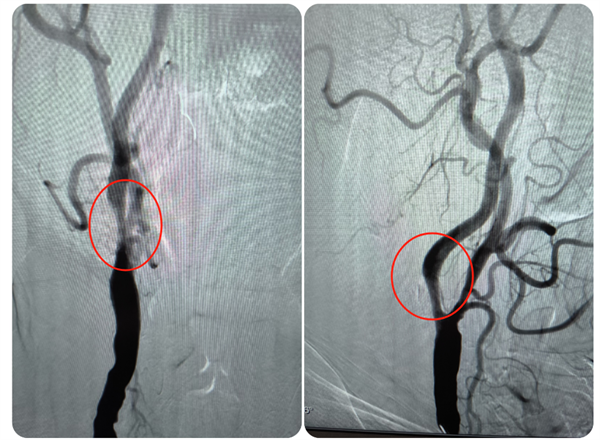

近日,老虎机app (简称老虎机app )神经外科主任钟书带领团队,应用光学相干断层扫描(OCT)技术,为一名颈内动脉颅外段夹层动脉瘤合并颅内段重度狭窄的患者进行了介入治疗手术,这也是我院神经外科完成的首例OCT手术,标志着科室在颈动脉夹层动脉瘤血管内治疗方面的技术水平再上新台阶,也为脑动脉瘤、脑血管狭窄等患者的诊断治疗提供了新选择。患者陆先生(化名)今年74岁,1...